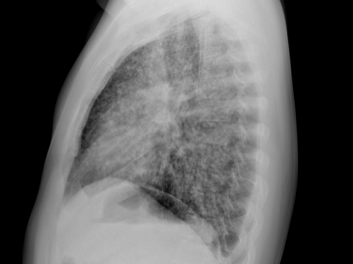

2) Imaging pearls—nodular pattern recognition

• Ask three things: craniocaudal distribution, symmetry, central vs peripheral.

• Centrilobular (spares pleura/fissures): airway-centered (e.g., NTM, bronchiolitis, tree-in-bud).

• Perilymphatic (tracks fissures/pleura & septa): sarcoid, lymphangitic spread.

• Random/diffuse (involves pleural surfaces): hematogenous spread → think miliary TB, disseminated fungal, septic emboli, metastatic disease.

• Interval change matters: new cavitation and confluence can upweight infection or aggressive malignancy.